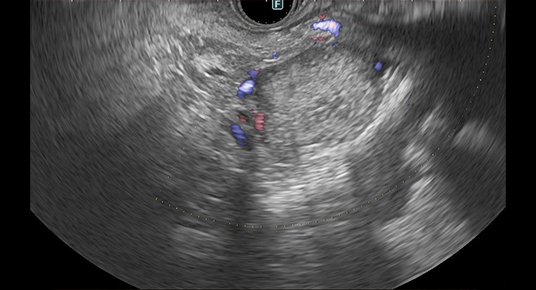

• 検査のイメージ

着色処理前

着色処理後